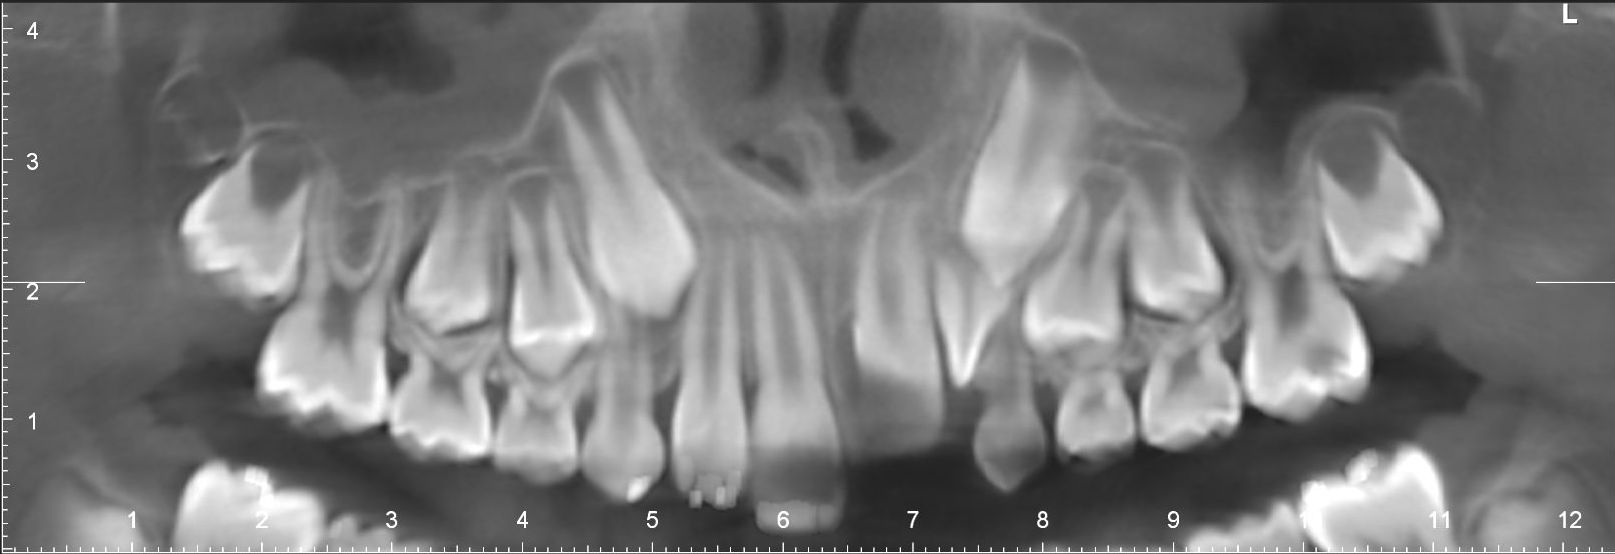

Images de panoramiques dentaire:

- C’est un examen extrêmement fréquent chez les enfants qui ont des problèmes orthodontiques.

Cet examen est fait le plus souvent chez l’enfant dans les bilans d’orthodontie.

Il peut être fait également chez l’adulte dans la même indication.